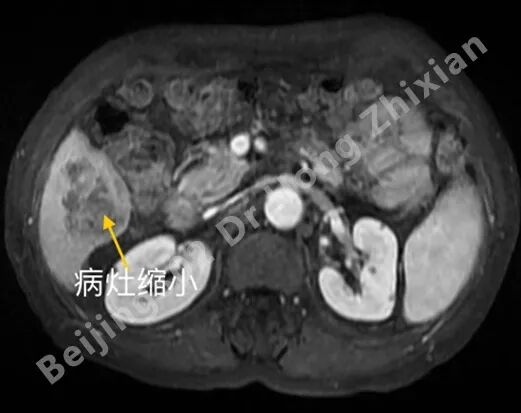

临床随笔丨肝癌术前新辅助治疗:“更优选择”还是“过度治疗”?